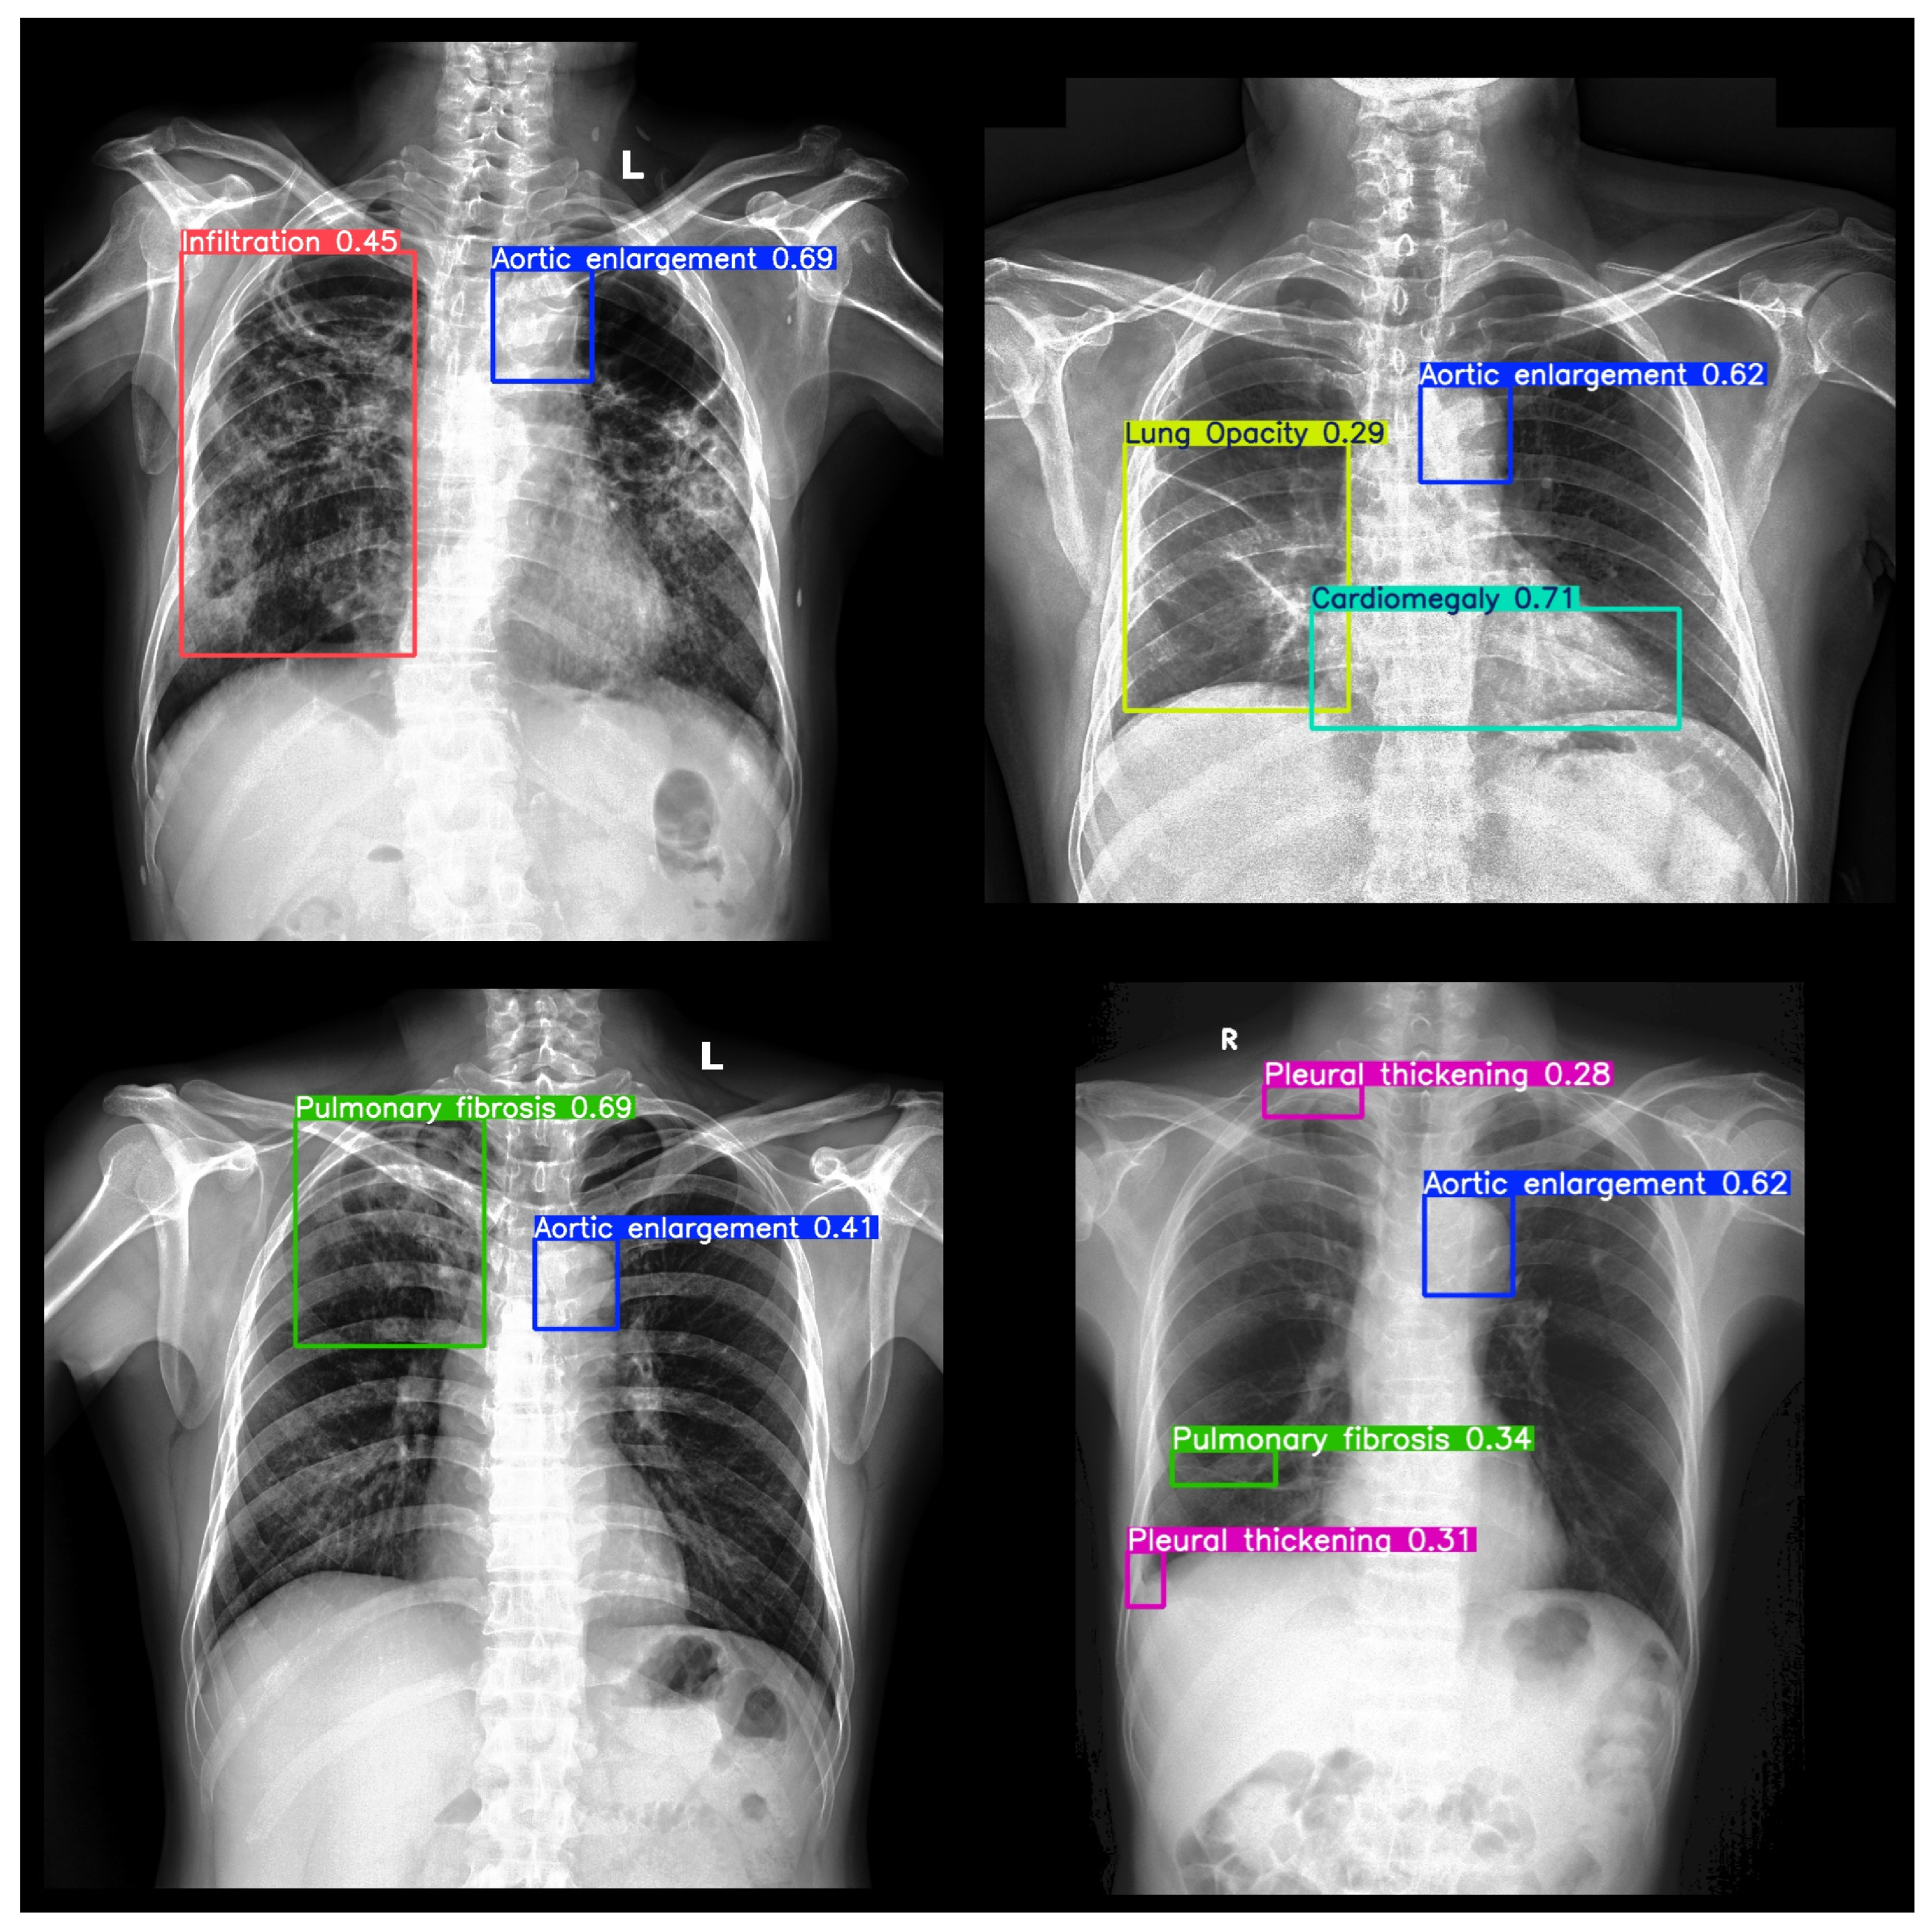

Loss convergence (Figure 2) indicates stable training across all components. Qualitative examples in Figure 3 confirm YOLOv8n’s ability to accurately localize multiple conditions, including co-occurrences like Cardiomegaly and Pleural Effusion. However, smaller pathologies (e.g., Nodule/Mass) were frequently missed, revealing limitations in spatial sensitivity.

Figure 3. Sample detection outputs from YOLOv8n showing bounding boxes for multiple co-occurring thoracic abnormalities.

Applsci 15 09345 g003